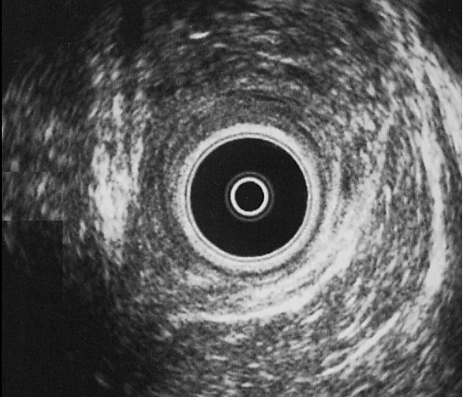

CANAL ANAL ALTO: Defecto posterior a las 7 h de la rama derecha del puborrectal